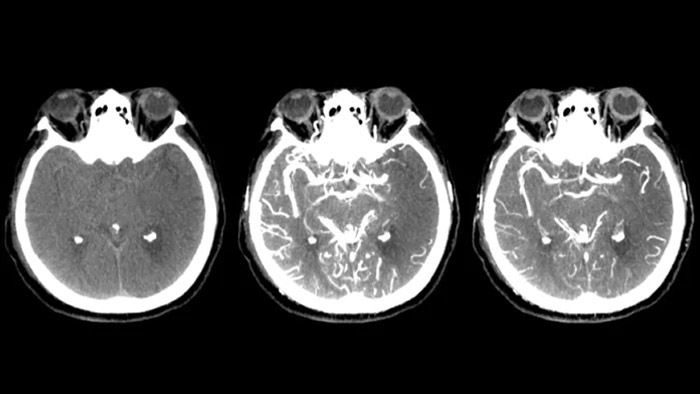

Drei SmartCT Aufnahmen

CT-artige Darstellung

SmartCT Soft Tissue generiert eine CT-artige Darstellung des Weichgewebes und erleichtert die Schlaganfalldiagnose auf drei Arten: Ein kontrastmittelfreier Scan hilft bei der Erkennung früher ischämischer Veränderungen. Ein Scan der frühen Phase hilft bei der Identifizierung des proximalen Verschlusses. Ein kontrastmittelverstärkter Scan der Spätphase unterstützt die Erkennung von Kollateralen.

Darstellung der kollateralen Füllung

Dual View zur Anzeige der Cone-Beam-CT-Volumina der Früh- und Spätphase nebeneinander verbessert die Erkennung der Penumbra und ermöglicht die Darstellung der kollateralen Füllung.